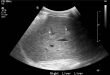

Повышенная эхогенность печени